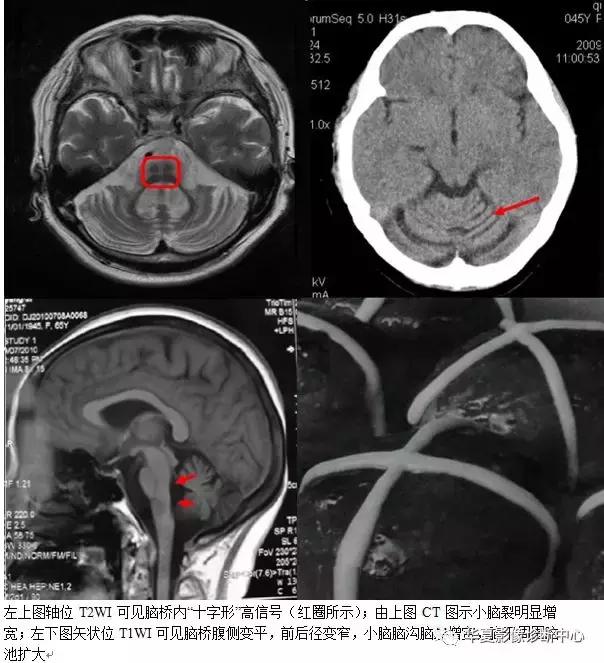

十、十字征

即MRI的T2加权像上脑桥的十字形异常高信号影,见于橄榄桥小脑萎缩(OPCA)患者,在多系统萎缩(MSA)其他亚型也可出现。由于MSA临床表现复杂,很难做出早期诊断。因此,“十字征”对MSA的诊断及分型具有重要作用。表现为不同程度的帕金森综合征、小脑性共济失调和自主神经功能障碍的重叠组合。根据受累部位的先后及临床表现的不同,可以分为不同的临床亚型。其病理主要是小脑、桥脑、下橄榄核萎缩,神经细胞脱失伴胶质增生。脊髓后索、橄榄脊髓束、皮质脊髓束以及脊髓小脑束变性,克拉克柱细胞及前角细胞脱失,亦可累及红核、黑质、基底节及大脑皮质。临床上可有小脑、自主神经、锥体外系、锥体束等多系统受累的临床症状和体征。该患者为老年女性,起病隐袭,进行性加重。以锥体外系(静止性震颤,四肢张力增高)及小脑症状(行走不稳、动作不协调)表现突出,后出现自主神经功能紊乱(尿便障碍)及延髓症状(构音障碍、吞咽困难)。因患者既往有明确高血压病史,同时发病年龄在绝经期后,故病程中无直立性低血压、性功能障碍表现。重要的是,患者发病过程中曾服用“美多巴、安坦”药物控制震颤及缓解肌张力增高,但无明显疗效,进一步支持MSA的诊断。结合患者头部MRI,可确诊为MSA。有研究资料表明,无论以锥体外系或小脑受累为主要临床表现,自主神经受累总是在此之前或与之同时出现。但是临床实践也发现MSA患者即使影像学表现正常,亦不能排除纹状体黑质病变可能,有关文献报道,单光子发射型计算机体层摄影(SPECT)结合MRI有助于提高MSA。

MSA分型中以OPCA患者的头部MRI表现“十字征”居多,OPCA典型的幕下形态学改变是橄榄、桥脑腹侧及小脑中脚和小脑萎缩。橄榄萎缩导致延髓腹侧上部变平,延髓桥脑沟变浅。桥脑萎缩最为常见。以桥脑腹侧改变为著,被盖部改变不明显。小脑中脚常有萎缩,这是桥脑-小脑束易被累及的影像学体现。小脑萎缩以小脑半球,特别是其前部改变较为明显。小脑和脑干萎缩往往继发四脑室和邻近脑池扩大,而脑池改变以桥前池增宽最为常见,桥小脑脚池、小脑延髓池增宽次之。国外有学者把“十字征”的演变过程分为6期:0期为正常;Ⅰ期为脑桥开始出现垂直的高信号影;Ⅱ期为出现清晰的垂直高信号影;Ⅲ期为继垂直线后开始出现水平高信号影;Ⅳ期为清晰的垂直线和水平线同时出现;Ⅴ期为水平线前方的脑桥腹侧出现高信号,或脑桥基底部萎缩引起的腹侧脑桥体积缩小,并发现水平线总是无一例外地继垂直线后出现。发现所有的OPCA患者在起病的2~3年内出现垂直的高信号影(达Ⅰ期),71%患者在5年内出现“十字征”(达Ⅳ期),7年内均达Ⅴ期。而且随着时间变迁在桥脑轴位T2WI上出现典型的“十字征”。国外学者认为“十字征”机制是脑桥核及桥横纤维变性。胶质增生致含水量增加,而由齿状核发出构成小脑上脚的纤维和锥体束未受损害,从而形成MRI上T2加权像上脑桥的十字形高信号影。有文献报道在MSA的三种临床亚型中均有类似征象。就本病而言,其临床症状的进展与影像学的变化相吻合,很好地展示了此病的演变与加重的过程。